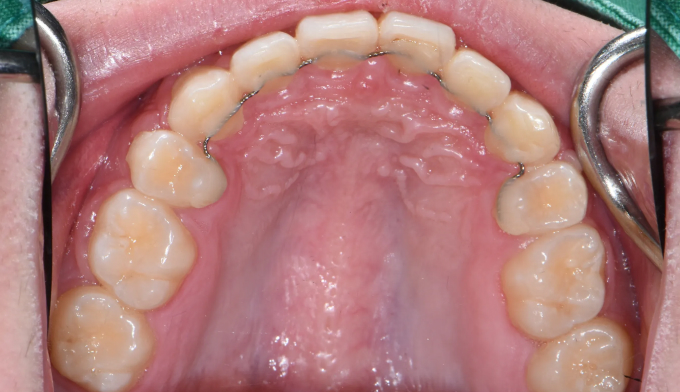

앞니가 돌출되어 있으면서 동시에 위 맨끝 어금니가 아래 어금니와 사선으로 물려있는 가위교합이 관찰됩니다.

가위교합은 음식물 섭취에 있어서도 비효율적이지만, 올바른 잇솔질을 하기가 어려워 구강위생에도 좋지 않아 교정이 필요합니다.